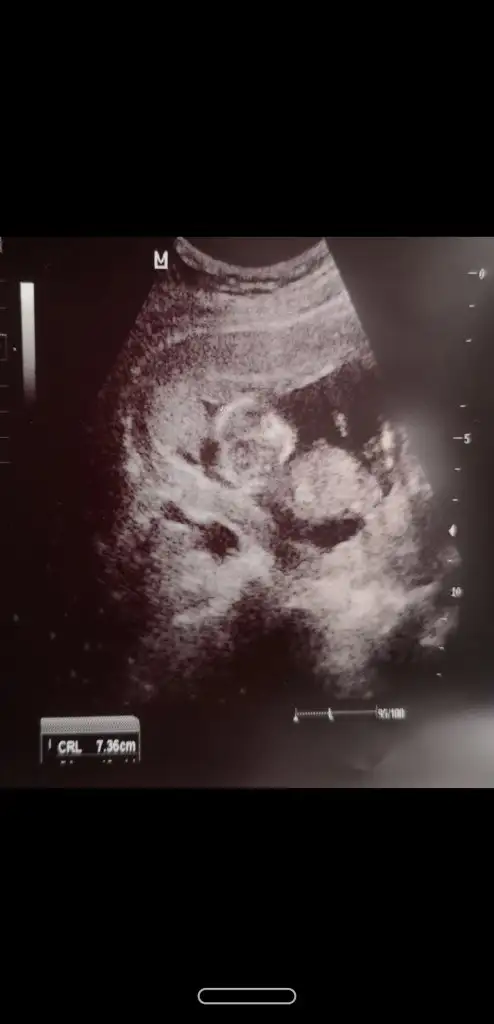

Merhaba bana da bi tahminde bulunur musunuz çok merak ediyorum🥰

11+2 haftası

Canım bi de bu var ,ben de bugün başka doktora gittim direkt erkek dedi emin mısınız dedim sanki pipi gördüm dedi ama bir ay sonra netlesir dedi :)

Kız tabiki burda ama sonraki büyük haftada nub olmaz ☺️ demekki kordon gelmiş yoksa diğeri net bariz kız nubu 🙈